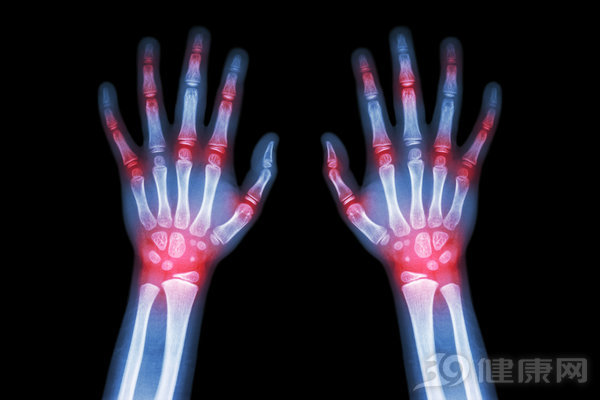

风湿是一种很让人头疼的疾病,在我们日常生活中比较常见,不少朋友都深受风湿的困扰。而风湿的发病人群以老年人为主,特别是在天气阴冷或下雨时会很痛苦。那么,风湿形成的原因是什么呢?

当肢节屈伸不利、活动受限时,也会诱发关节受到损伤,进而发展为关节僵直、畸形等问题。在外科骨关节门诊,多见于由此而出现的风湿患者。

当关节扭伤、外力导致的损作等情况时,引起关节气血阴滞、淤血凝积,未及时处理的,可出现肌肉、关节的局部肿胀、疼痛,如果治疗不及时或治疗未痊愈,是极易可能出现风湿问题的。